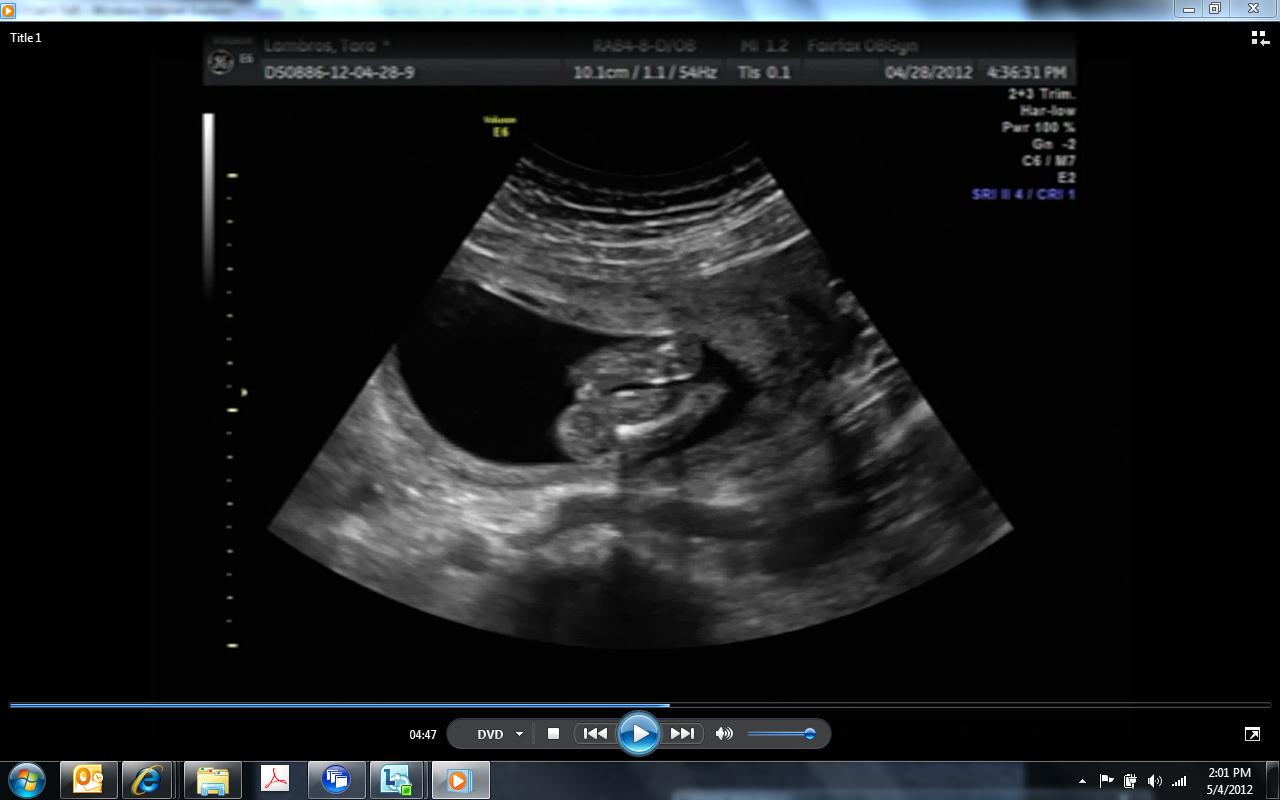

Sorry to post so much... but I'm watching the U/S in slow-mo and just noticed "something" in b/w the legs. I dont know why SO MANY look like "girl"...

Attachment 2415

Attachment 2416

I still think girl on the basis of the very first pic which is the only one that really has a clear shot of the goods. If that's a penis in between the legs in the pic directly above, your son would have a great future as a porn star LOL!! That's either cord (looks too thick tho) or the baby had bent over a bit at the waist and it's spine.